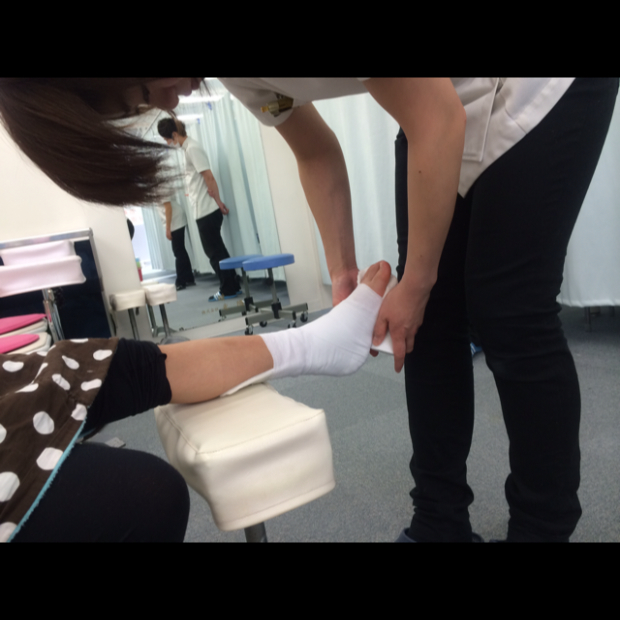

特に子供の場合はまずエコ-で骨折の有無を確認します

転んでしまったけがをしてしまたらまずは

接骨院でエコ-を見てみてください

藤川接骨院048-456-9339]]>